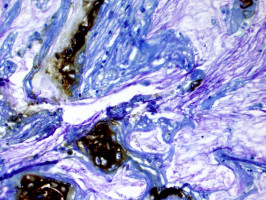

Image credit: Koushik Das, M.D.